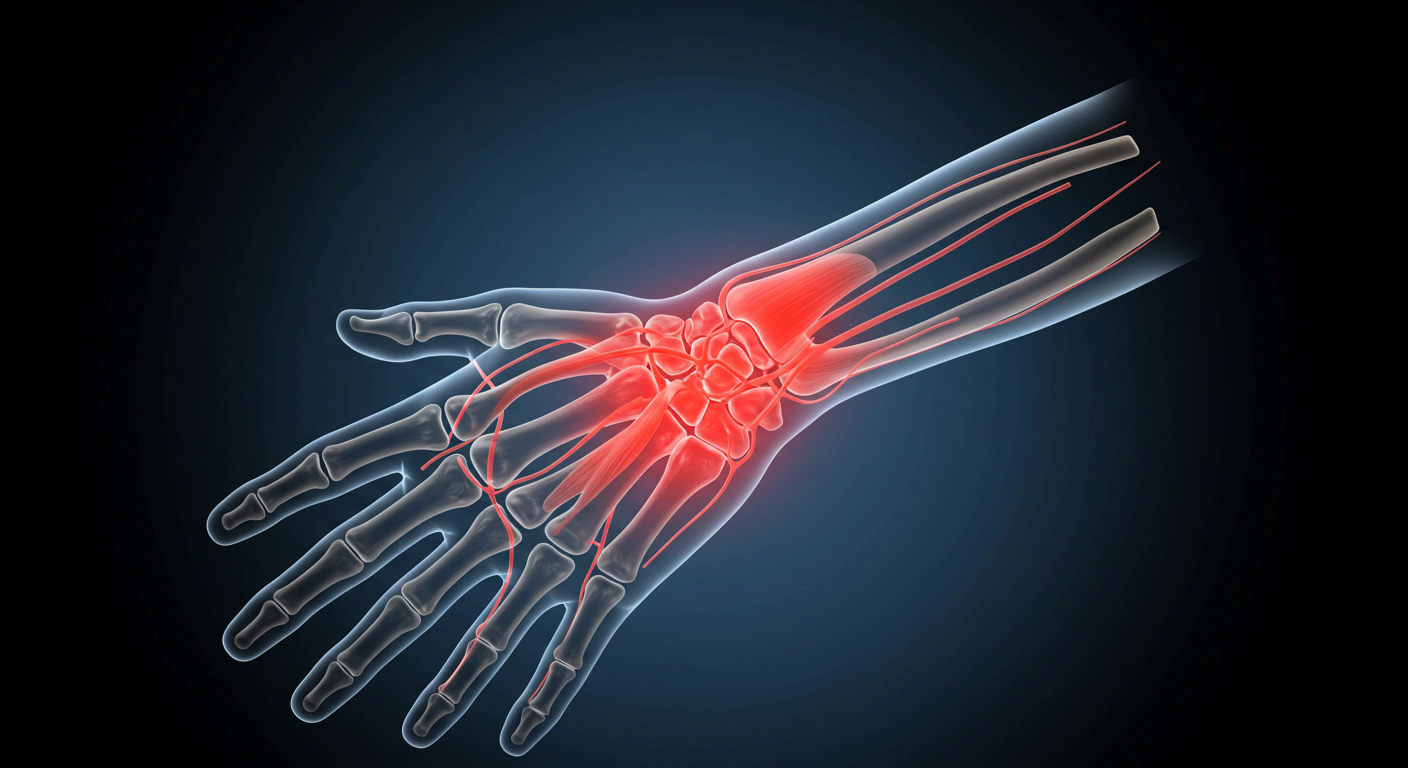

손목은 우리 손과 팔을 연결하는 중요한 관절로, 하루에도 수백 번씩 움직이게 됩니다. 키보드를 두드리거나 스마트폰을 스크롤하고, 물건을 들거나 청소를 하는 모든 행동에 손목이 관여하죠. 그런데 이런 반복적인 사용이 누적되면 손목에 미세한 손상이 반복적으로 축적되며 통증으로 이어질 수 있습니다.

1. 손목터널증후군 (수근관증후군)

손목에는 정중신경이라는 신경이 지나가는데, 이 신경이 반복적인 압박을 받으면 손가락 저림, 통증, 근력 약화 등의 증상이 나타납니다. 키보드, 마우스, 스마트폰 등을 자주 사용하는 사무직 근무자나 디지털 기기를 오래 사용하는 분들에게 흔히 나타나죠.

2. 건초염 (드퀘르벵 증후군)

손목 주변 힘줄을 싸고 있는 막(건초)에 염증이 생겨 발생하는 질환으로, 손을 자주 사용하는 주부, 요리사, 간호사 등에게 잘 나타납니다. 특히 엄지손가락과 손목이 연결되는 부분이 아프고, 물건을 들거나 비트는 동작이 힘들 수 있습니다.